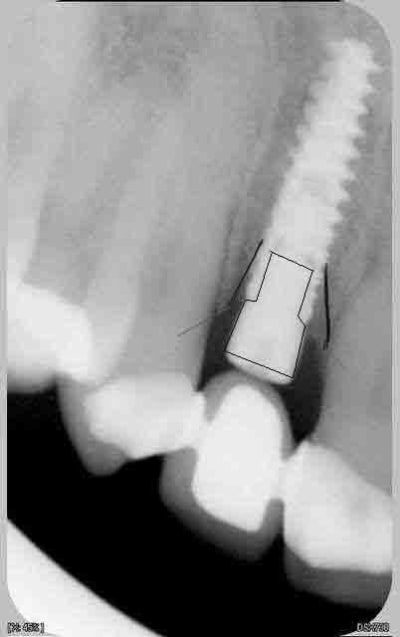

Attends, sur ces radios t'as 4 mm de perte osseuse? Les vis de cicatrisation sont en place non? Je devine la jonction implant/vis et y a quasiment pas de perte sur tes dernières radio. Enfin je connais pas bien le krestal et la forme de la vis.

Je veux dire, elle est où la perte osseuse sur cette radio? Mais tu as raison, on ne doit pas avoir les même exigences.

La cratérisation est visible beaucoup plus haute: surtout au sondage. L'os que tu vois est en palatin, en vestibulaire, il n'y a plus rien sur cette même longueur.

Sur la molaire, tu ne vois rien aussi.